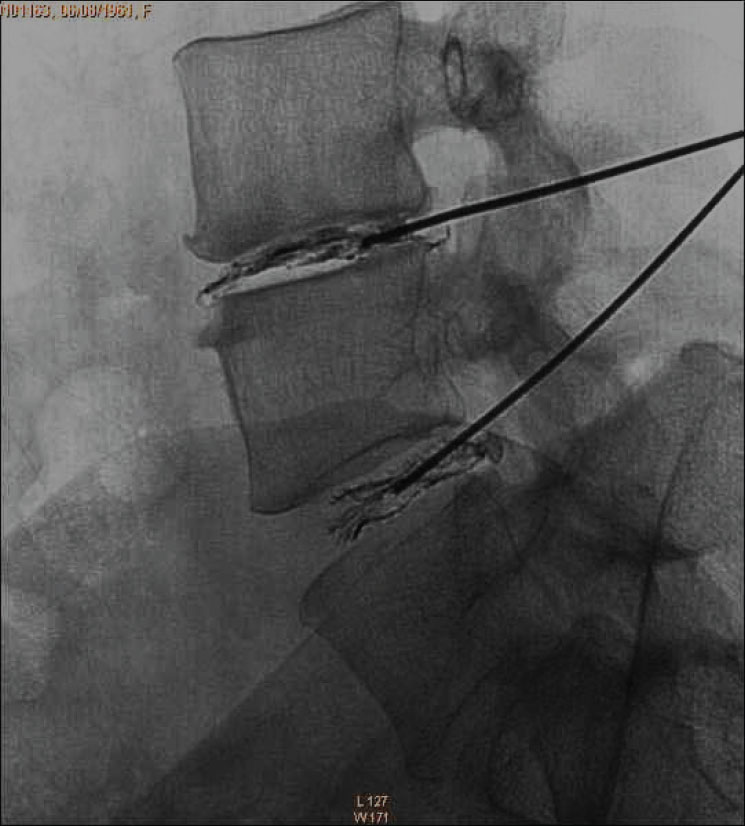

DiscoGel@ is a radiopaque gel implant, injected percutaneously into the nucleus pulposus.

• Micronized Tungsten allows the visualization of the gel progression under the fluoroscopic control where the injection flow can be observed.